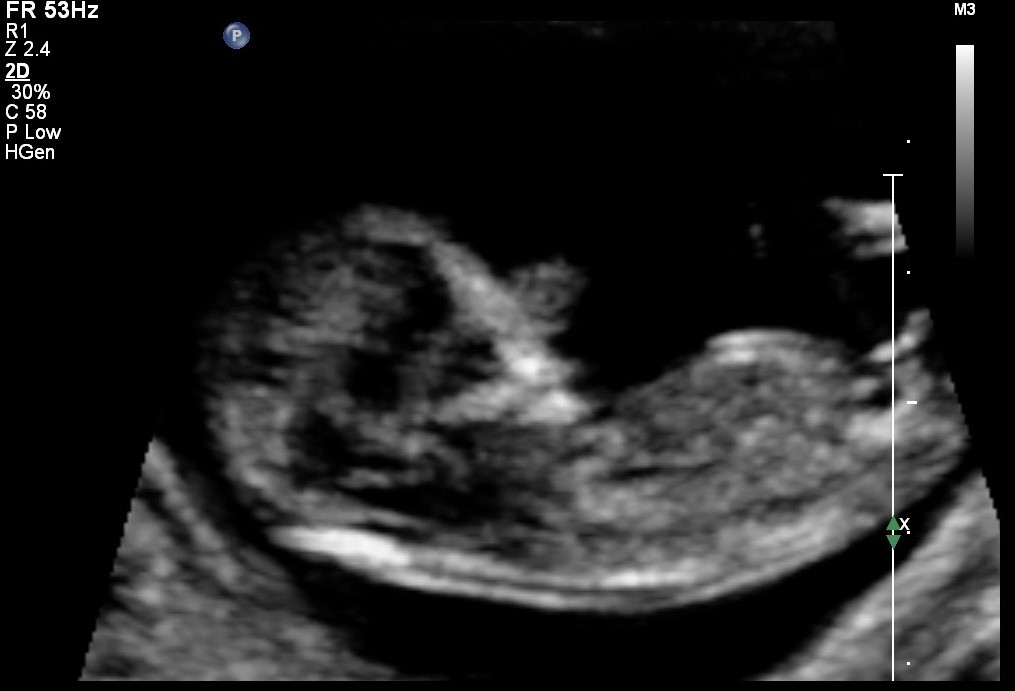

Im posting pics from my NT scan where i was 12 weeks along but baby measured 12w4days.. i have got mostly boy guesses but wud like to see what u all think. Attachment 25368Attachment 25369

I'm getting boy vibes for sure. The skull and nub both make me think boy!

very boyish pics xx

Definite boy nub

Thank you all for guessing...... Is there a chance of this boy nub turning into a girl? im in india and gender determination is illegal here ..im now 20 weeks but cant really ask the US tech to check the gender. Many people have guessed girl with the way im carrying so just wondering if a nub angled high can turn out to b girl...has it ever happened to anyone ?

at an angle THAT high I dont forsee you hearing girl. Anything is possible of course but at this point highly unlikely.

I severely doubt that this will turn into a girl. How you are carrying has nothing to say at all, nub is pretty accurate though! Don't listen to other people's guesses using unreliable theories. Maybe you can try and catch a glimpse of the gender at your scan? And if not, then you will have to wait until birth. I would definitely be counting on a boy though! It can be your little secret, let them talk. :cool: